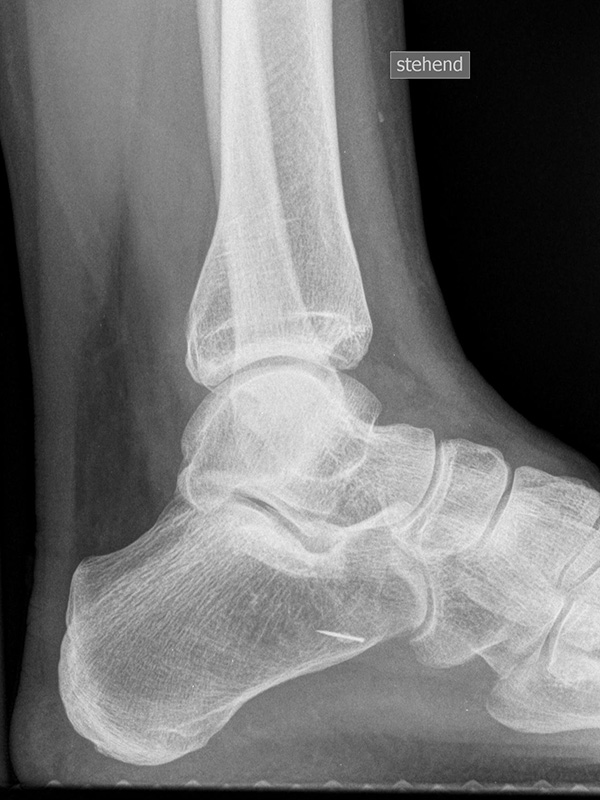

Sprunggelenk lateral mit Belastung

Positionierung:

• Der Patient steht, beide Beine sind geleichmäßig belastet.

• Der Zentralstrahl wird ist in Höhe des Gelenkspalts des OSG auf die dorsale Kante der Fibula zentriert.

• Die Kassette liegt medial dem Fuß an und ist parallel zur Fußachse ausgerichtet.

Kennzeichen des Röntgenbildes:

• Tibiagelenkfläche und Talusrolle werden exakt seitlich dargestellt, es kommt zu keinen Doppelkonturen.

• Die Fibula projiziert sich ins mittlere bis hintere Drittel der Tibiagelenkfläche.

• Die vordere und hintere Tibiakante, das Chopart-Gelenk und das Subtalargelenk kommen zur Darstellung. Das proximale Ende des Os metatarsale V ist mit abgebildet. Der Weichteilmantel (Achillessehne) ist erkennbar.

• In der belasteten Situation kommen insbesondere Verschiebungen von Talus gegenüber der Tibia zur Darstellung sowie eine Verschmälerung des Gelenkspalts.

Besondere Bemerkungen zum Beispielbild:

• Zustand nach Fremdkörperverletzung (2. Ebene zur Mortise-Aufnahme unter Belastung).

• Die röntgendichte Struktur (Metall) befindet sich plantar im Bereich des Kalkaneus.